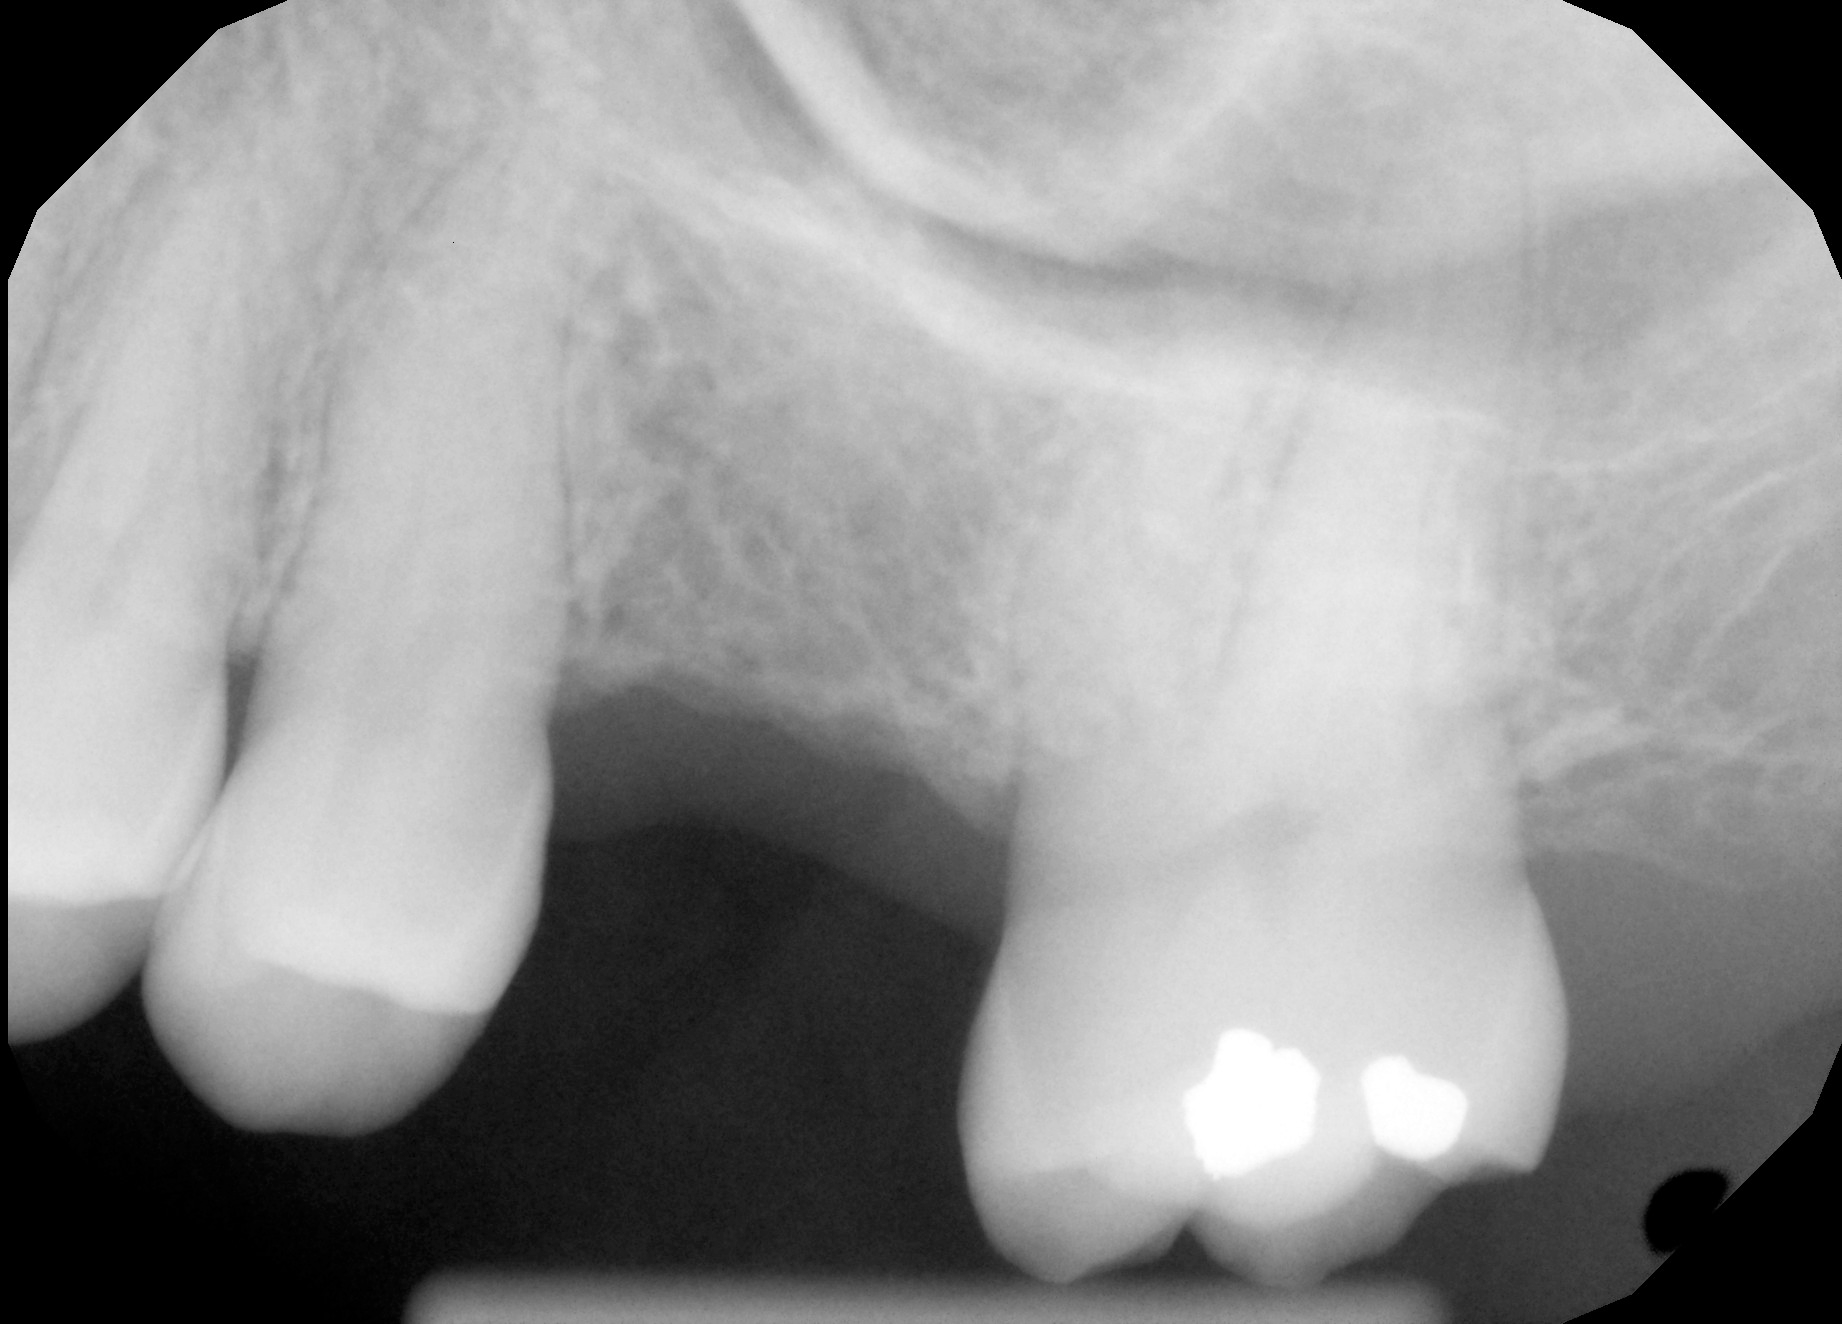

Radiographic Analysis (X-Ray)

Forensic identification of anomalous shape in extraction cavity.

Primary Exhibit

This featured x-ray, in my opinion, clearly shows an anomalous artifact embedded in my jawbone. This would have had to have been placed into the extraction cavity after the extraction and prior to suture. Dr. Patel is the only one who could have inserted this object - which appears to be a bioelectronic transceiver - into my jaw. Over time, the cavity fills with bone tissue, so the implant is now embedded in the jawbone.